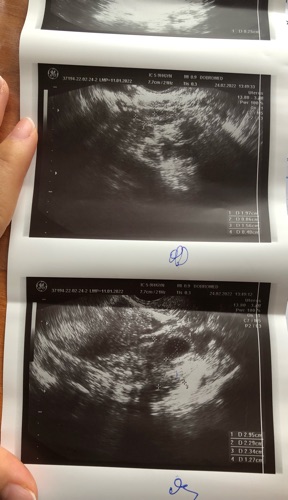

Chào bác sỹ ạ, hôm nay em có đi khám thì thai được 5,5 tuần, tuy nhiên, bác sỹ có thông báo là thai chưa vào tử cung, nghi thai ngoài ạ. Hiện tại em đang ở nước ngoài nên cũng có nhiều khó khăn ạ. Nếu có thể, bác sỹ có thể giúp em xem lại hình ảnh siêu âm và đưa ra kết luận được không ạ? Em cảm ơn nhiều ạ!

Khả năng cao là thai ngoài rồi em nhé. Khi siêu âm bs quan sát sự di động của cơ quan nữa nên bs kết luận thì em nên tin tưởng nhé

Ngày đầu kì kinh cuối 14/01 mà kinh e đều thì giờ cũng phải hơn 5 tuàn là thai phải vào buồng tử cung r em ạ

Dạ em đã đi khám lại, thai vào tử cung rồi ạ, không phải thai ngoài ạ. Cảm ơn bác sỹ!